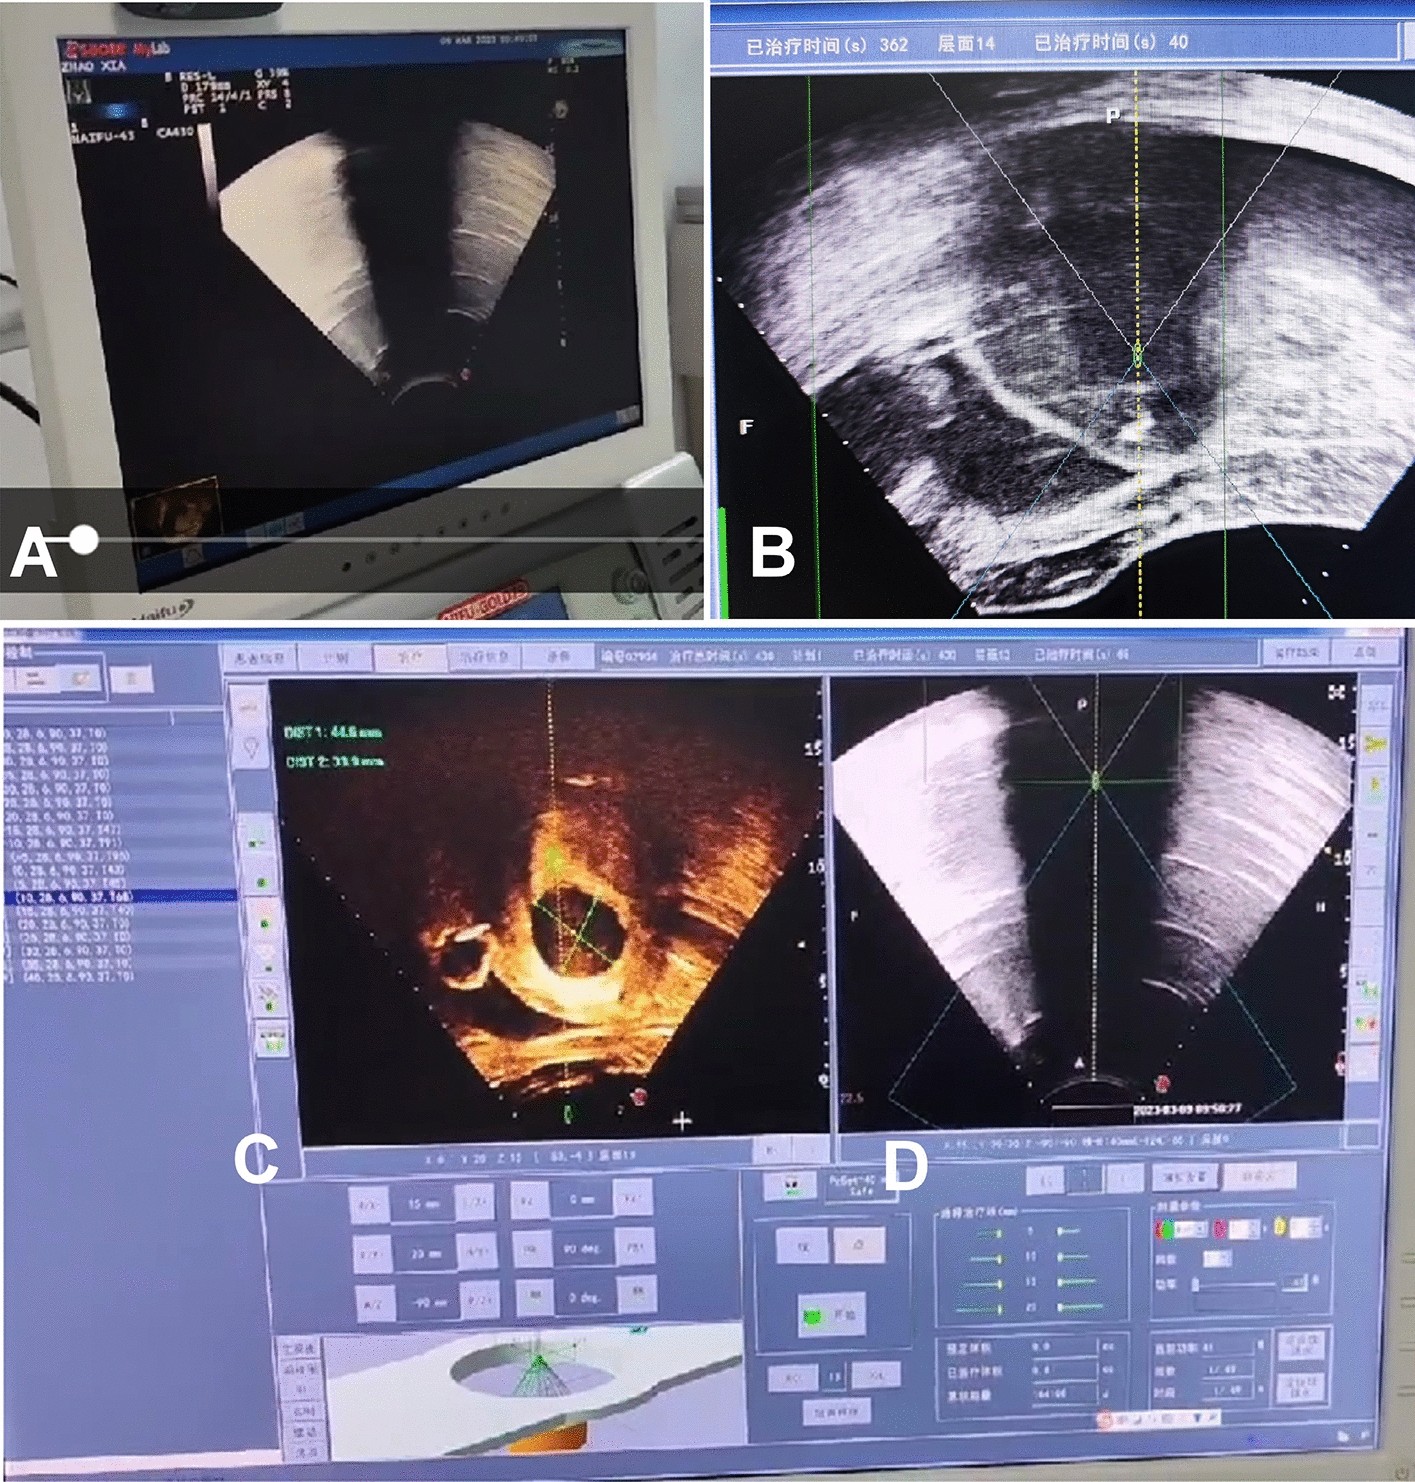

Figure 1

Real-time ultrasound monitoring of treatment of uterine ademomyosis with high-intensity focused ultrasound (HIFU). (A) Imaging of real-time ultrasound monitoring was displayed on the screen of one ultrasound scanner. (B) Real-time ultrasound monitoring showed that the total treatment time was 362 s, the treatment was on the 14th layer, and the treatment time on this layer was 40 s. (C) HIFU treatment imaging was displayed on the monitor screen of HIFU scanner. (D) The imaging of real-time ultrasound monitoring (A) was transferred to the HIFU screen (D) for real-time monitoring of the HIFU treatment effect, and if the treatment caused significant gray increase in the whole lesion area, the HIFU treatment would be stopped.